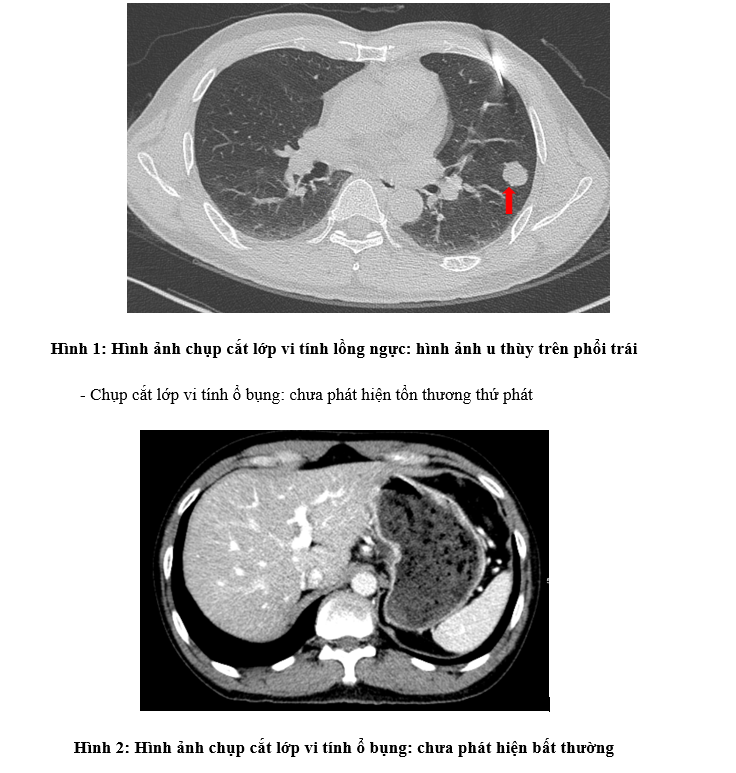

– Chụp cắt lớp vi tính lồng ngực: khối thùy trên phổi trái tỷ trọng tổ chức có phế quản chứa khí, có vôi hóa, 23x25mm, bờ tròn

Bệnh sử: Tháng 3/2023, bệnh nhân được chẩn đoán ung thư trực tràng cao đã phẫu thuật cắt đoạn đại trực tràng + vét hạch tại tại Bệnh viện Quân y 110. Giải phẫu bệnh sau mổ: ung thư biểu mô tuyến biệt hóa vừa xâm nhập lớp cơ, 3/3 hạch viêm mạn tính. Sau đó bệnh nhân được theo dõi định kỳ -> Tháng 5/2024 bệnh nhân xuất hiện đau ngực trái âm ỉ, kèm ho khan, không ho ra máu, không khó thở, không đau bụng, đại tiện bình thường, đi khám được chụp cắt lớp vi tính lồng ngực phát hiện nốt ở phổi trái kích thước 23x25mm, sinh thiết, giải phẫu bệnh và hóa mô miễn dịch: ung thư biểu mô tuyến di căn nguồn gốc đại trực tràng, BRAF (-), KRAS (+). Sau đó bệnh nhân được nhập viện vào Trung tâm Y học hạt nhân và Ung bướu – Bệnh viện Bạch Mai.